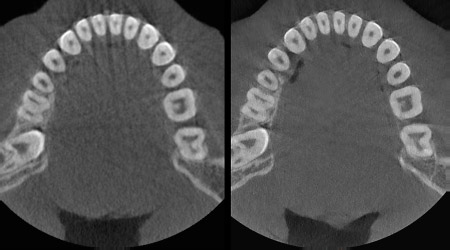

TECNOLOGÍA CS MAR

La tecnología CS MAR1 (reducción de artefactos metálicos) reduce significativamente los artefactos metálicos y permite comparar imágenes de forma dinámica.